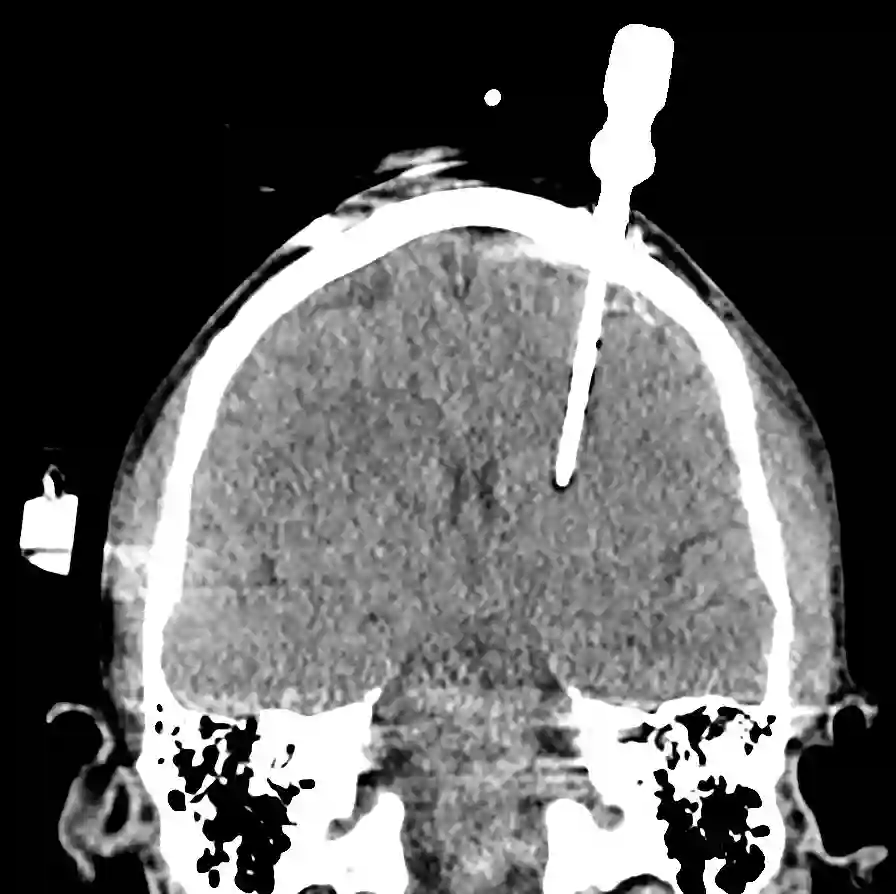

Eine externe Ventrikeldrainage, welche im klinischen Alltag auch als EVD bezeichnet wird, dient der externen Ableitung von Liquor. Es handelt sich um einen dünnen und röntgendichten Kunststoffschlauch (meistens aus Polyurethan), welcher über ein Bohrloch in die inneren Ventrikelräume platziert wird und nach extern abgeleitet wird.

Externe Ventrikeldrainagen können zum einen im Operationssaal oder auch direkt am Patientenbett eingelegt werden. Es bestehen zwei verschiedene Arten, um eine platzierte EVD zu fixieren. Zum einen kann eine EVD über eine Tunnelierung ausgeleitet und fixiert werden oder über einen Bolt, welcher direkt in das angelegte Bohrloch eingeschraubt wird. Als üblicher Zielpunkt für die Einlage ist das ipsilaterale Vorderhorn des Seitenventrikels.